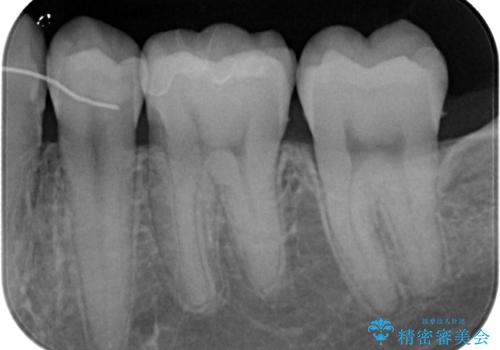

- セラミックにやり替えたいとのことで来院された患者様です。検査の結果、レントゲン上でメタルインレーの不適合を認めたのでセラミックインレーによる修復治療を行っていくことにしました。

拡大鏡視野下で、メタルインレー、虫歯の除去を行い、セラミックインレーに適した形に整えました。

歯と歯茎の間に圧排糸と言われる糸を入れてシリコーン印象材にて精密な型どりをしました。

セラミックインレーの装着時には、唾液の侵入を防ぐために、ラバーダム防湿を行いました。